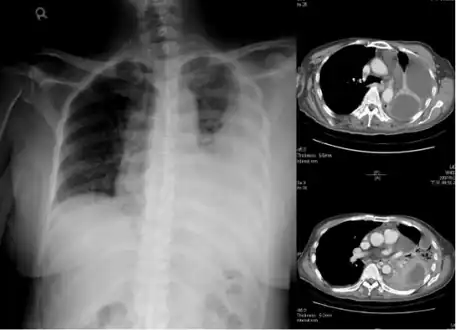

Lungs

Empyema with abscess